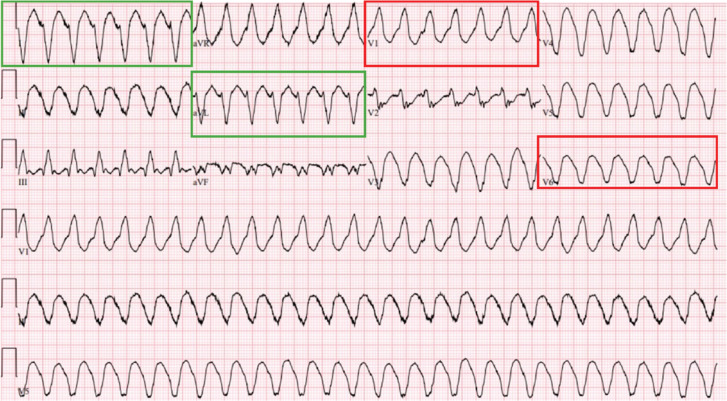

室性心动过速(VT)是一种危及生命的心律失常,具有高发病率和死亡率,特别是在结构性心脏病患者中。射频消融术是治疗这种恶性心律失常的有效方法。我们报告三例成功终止VT使用独特的导管消融技术。通过这些病例和技术,我们强调了在心脏层内异常电路的特定定位以及心动过速终止的电图证据的优势。

Ventricular tachycardia (VT) is a life-threatening arrhythmia associated with high morbidity and mortality, particularly in patients with structural heart disease. Radiofrequency ablation is an effective procedure to treat patients with this malignant arrhythmia. We report three cases of successful termination of VT using unique catheter ablation techniques. Through these cases and techniques, we highlight the advantages of specific localization of abnormal circuits within the cardiac layer involved, as well as electrogram evidence of tachycardia termination.